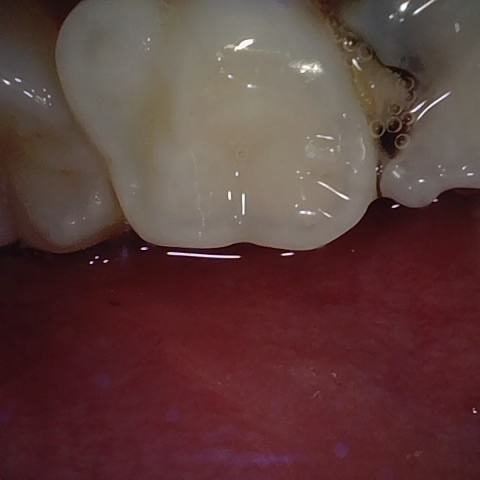

Annotated as "Good"